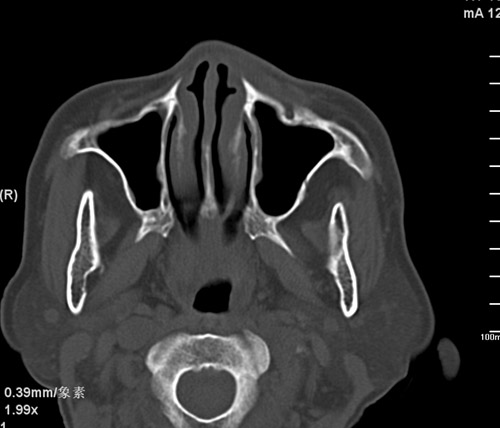

标题: CT17755:女,74 左鼻旁肿胀半年,临床以左上颌窦旁占位行CT [打印本页]

标题: CT17755:女,74 左鼻旁肿胀半年,临床以左上颌窦旁占位行CT

ct考虑鼻前庭囊肿 或鼻翼基底部慢性炎症,左上颌窦少许炎症 请指教

1)考虑左侧鼻前庭囊肿并感染。2)双侧上颌窦炎。

左侧鼻前庭囊肿并感染。双侧上颌窦炎。支持